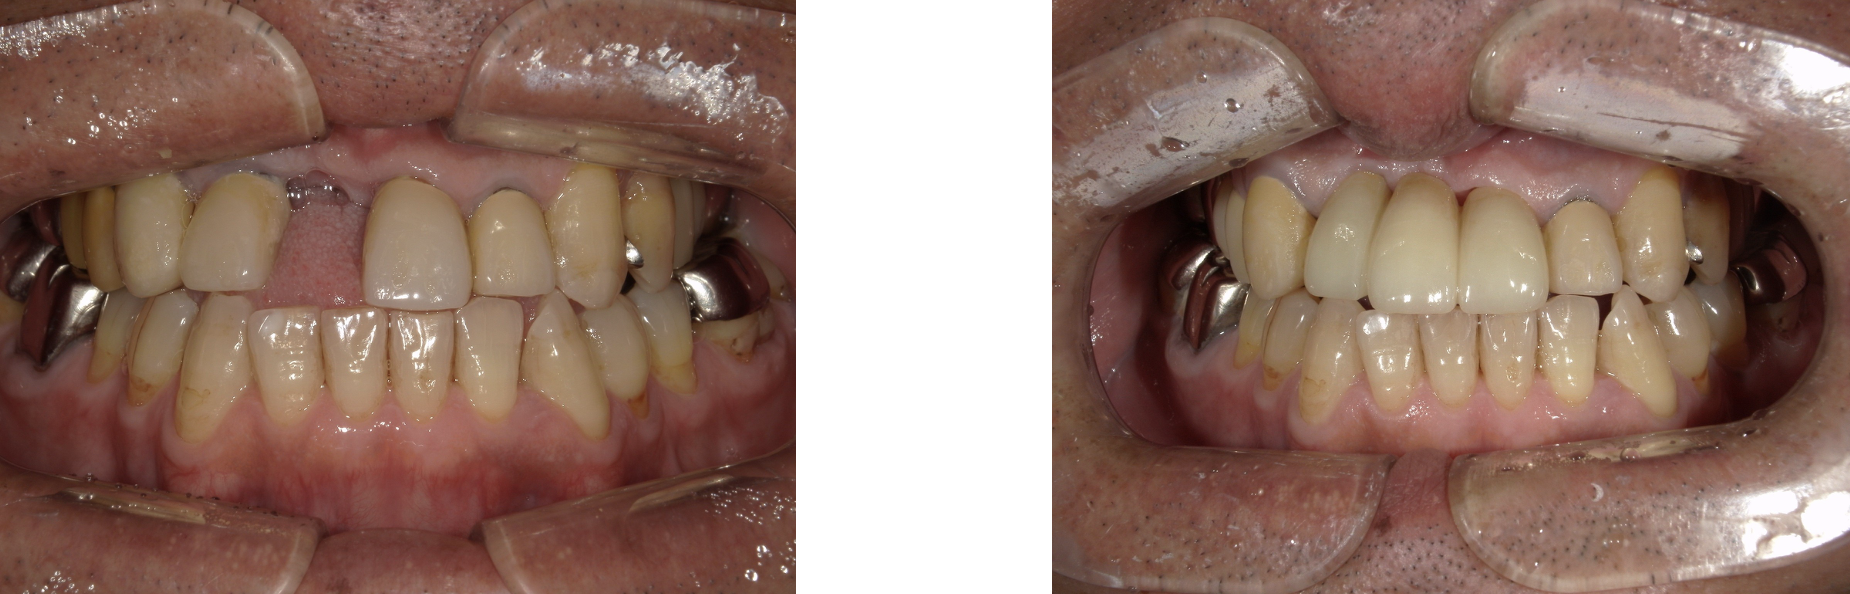

ジルコニアセラミックブリッジ 症例2

ジルコニアセラミックブリッジを前歯に入れた症例